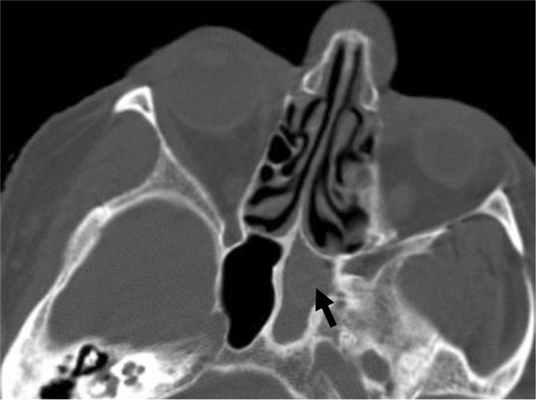

Во всех изученных случаях в околоносовых пазухах определялись высокоплотные включения. Одна группа включений в виде четко очерченных единичных и довольно крупных очагов уплотнения, которые определялись в костном окне просмотра изображений была выявлена у 11 (37,9%) человек, другая — в виде множества мелких нечетко очерченных очагов, которые не определялись или определялись плохо в костном окне просмотра изображений, — у 18 (62,1%) пациентов (рис. 6). Рис. 6. Больная М., 75 лет. КТ в аксиальной проекции. Правосторонний грибковый сфеноидит (указано черной стрелкой). В мягкотканном окне определяются мелкие множественные гиперденсивные включения (а), которые в костном окне не определяются (б). Left-had mycotic sphenoiditis (indicated by the black arrow). Multiple hyperdense inclusions can be seen in the soft tissue window (a) undetectable in the bone window (b).

Зона переходной плотности (зона гало), окружающая включения, определялась в 17 (58,6%) случаях: у 4 (23,5%) пациентов при одиночных и крупных высокоплотных очагах, у 13 (76,5%) больных при включениях в виде множества мелких нечетко очерченных очагов (рис. 7). Рис. 7. Больная Н., 80 лет. КТ в аксиальной проекции. Fig. 7. Patient А., aged 80 years. X-ray computed tomography in the axial projection. Правосторонний грибковый сфеноидит (указано белой стрелкой). В мягкотканном окне вокруг гиперденсивного центра определяется зона переходной плотности (зона гало). Right-had mycotic sphenoiditis (indicated by the white arrow). The zone of transition density around the hyperdense centre can be seen in the soft tissue window (the halo zone).

В 15 (51,7%) случаях отмечалось локальное утолщение прилежащих к мягкотканному содержимому костных структур (рис. 8). Рис. 8. Больная Т., 85 лет. КТ в аксиальной проекции. В костном окне отмечаются левосторонний сфеноидит со слабо гиперденсивным грибковым телом (указано черной стрелкой) и утолщение прилежащих костных структур. Left-hand sphenoiditis with the weakly hyperdense fungal bone visible in the bone window. (indicated by the black arrow) and thickening of the adjacent bone structures. У 1 больного это появилось через 2 мес после первичного исследования. В 1 случае определялось асимметричное утолщение прилежащих костных структур среднего носового хода.